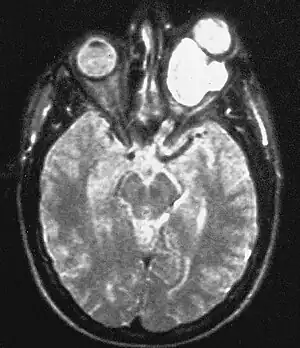

| Magnetic resonance image of a large retrobulbar optic nerve tumor causing massive proptosis | |

Optic nerve gliomas have low mortality but extremely high prevalence of vision loss & eye-bulging exophthalmos) in children.[4] As of 2014, approximately 1000 cases had been reported.[4]

Optic nerve gliomas are diagnosed using magnetic resonance imaging (MRI) and CT scans.[6] The tumor adopts a fusiform appearance, appearing wider in the middle and tapered at the ends.[6] Enlargement of the optic nerve along with a downward kink in the mid-orbit is usually observed.[6] While CT scans allow for optic nerve evaluation, MRI allows for intracranial evaluation to observe if the tumor has extended to other regions such as the optic chiasm & hypothalamus.[7]